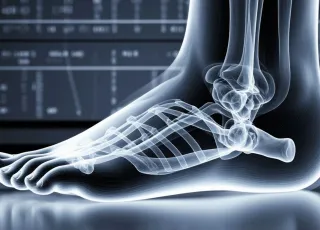

Причины развития патологий разнообразны — от воспалительных изменений до аутоиммунных болезней. Требуется целый комплекс диагностических мероприятий для постановки диагноза. Одним из наиболее информативных методов является магнитно-резонансная томография. МРТ позволяет визуализировать детальное анатомическое строение, что значительно ускоряет диагностический поиск.

МРТ позволяет получить огромное количество информации об исследуемой области. Существует много протоколов диагностики заболеваний со стороны коленного, тазобедренного, лучезапястного, голеностопного и других суставов.

Томография позволит выявить воспалительные и инфекционные процессы, повреждение костных структур или связочного аппарата, наличие патологической жидкости в суставной капсуле, дегенеративные болезни, опухоли. Для повышения диагностической мощности исследования врач может прибегнуть к применению контрастного вещества.